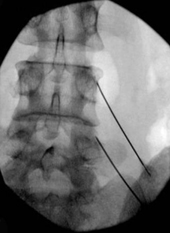

無論是高頻熱凝神經阻斷術還是射頻脈衝式神經調控,都需要醫師在超音波或 X 光的影像引導下,將一根或數根特殊的治療電極針插入欲治療之部位,並透過特殊電極將高頻能量傳導到電極針的末端。這個過程中,電磁波會在針尖附近的組織細胞中產生能量,進而造成熱凝或電磁效應。這些變化會破壞該區域的痛覺神經或讓其對疼痛的感覺變得遲鈍,進而達到止痛效果。

高頻熱凝神經阻斷術/射頻脈衝式神經調控示意圖